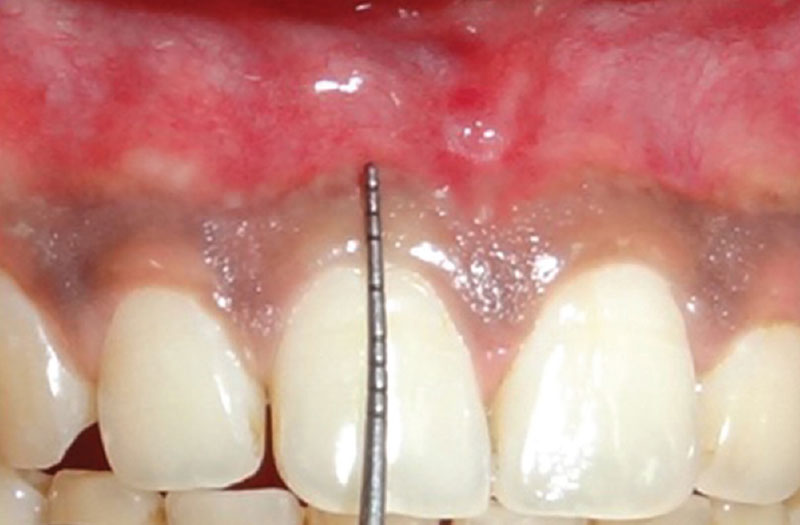

Attached gingiva

Firm, dense, and often stippled soft tissue that is tightly bound to underlying periosteum, bone, or a natural tooth.

Gingiva lying between the free gingival groove and the mucogingival line. It is firmly attached by lamina propria to underlying periosteum, bone, and tooth.